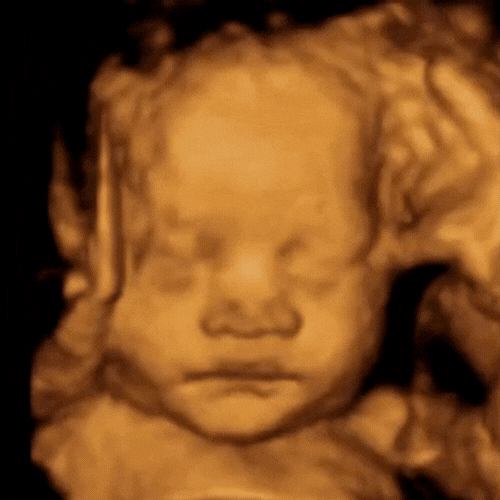

ScanSanctuary Client Scan Examples

If baby is in a favourable position then we may be able to show you a 4D preview and confirm baby’s gender (if we do not see these things then you will not be offered a discounted rescan, since they are not the primary focus of this scan).

Our state-of-the-art technology (GE Voluson Swift) is one of the most popular ultrasound machines for obstetric scanning. It features class leading 4D imaging as well as proprietary GE efficiency technologies. 3D/4D imaging modes, CrossXBeam and Speckle Reduction imaging assist with excellent accuracy.